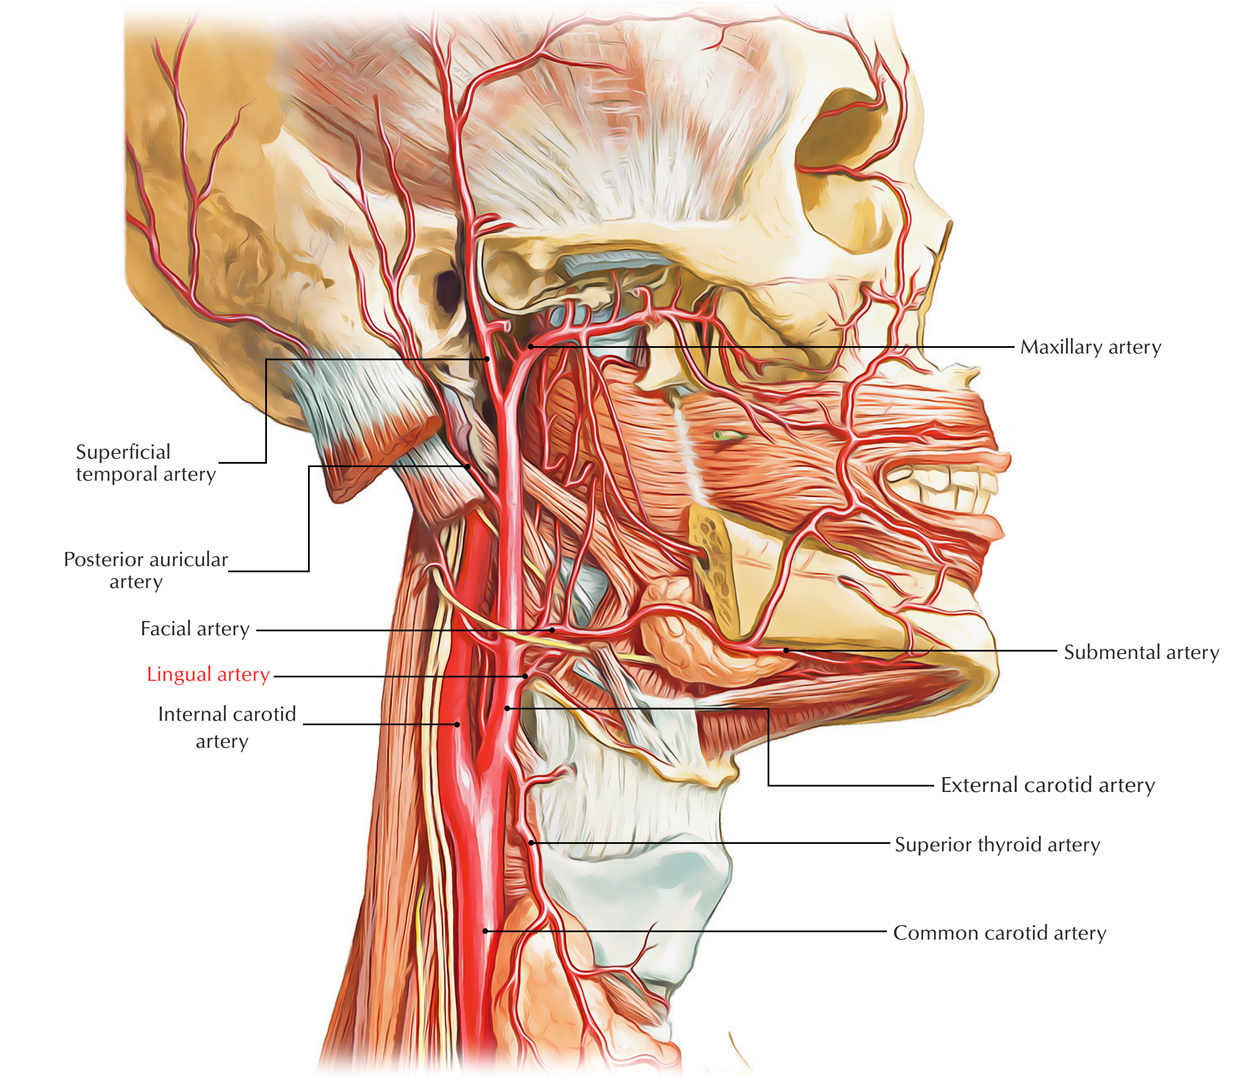

Анатомия внутренней яремной вены: КТ изображения